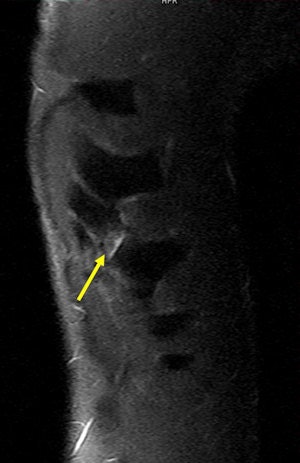

Other injuries that can be sustained during rugby matches occur in the thoracic spine, most likely secondary to a blow to the back or fall on the back. In rare cases, internal organs may be injured, but these are secondary to sternal/rib injuries. Cardiac contusion/tamponade and pneumothorax/hemothorax may also occur.

Rib injuries among rugby players tend to be most common in the fifth and ninth ribs, and they are often missed with conventional radiography and ultrasound. Always perform a CT scan with a multiplanar reconstruction (MPR) and volume-rendering technique (VRT), and use both CT and MRI for the acute stage, recommends Hayashi and his co-authors from the department of radiology at Klinikum Augsburg, Germany, the Australian Sports Commission, and Drs. Van Wageningen & Partners, Somerset West, South Africa. It is also necessary to consider nuclear medicine imaging for the delayed stage.

For an MRI examination of a suspected rib injury, the patient should be in a prone position, a marker should be placed, and axial and oblique coronal STIR (short TI inversion recovery) sequences should be obtained. T1-weighted sequences are not useful, and artifacts can be expected due to pulsation and breathing, they stated.